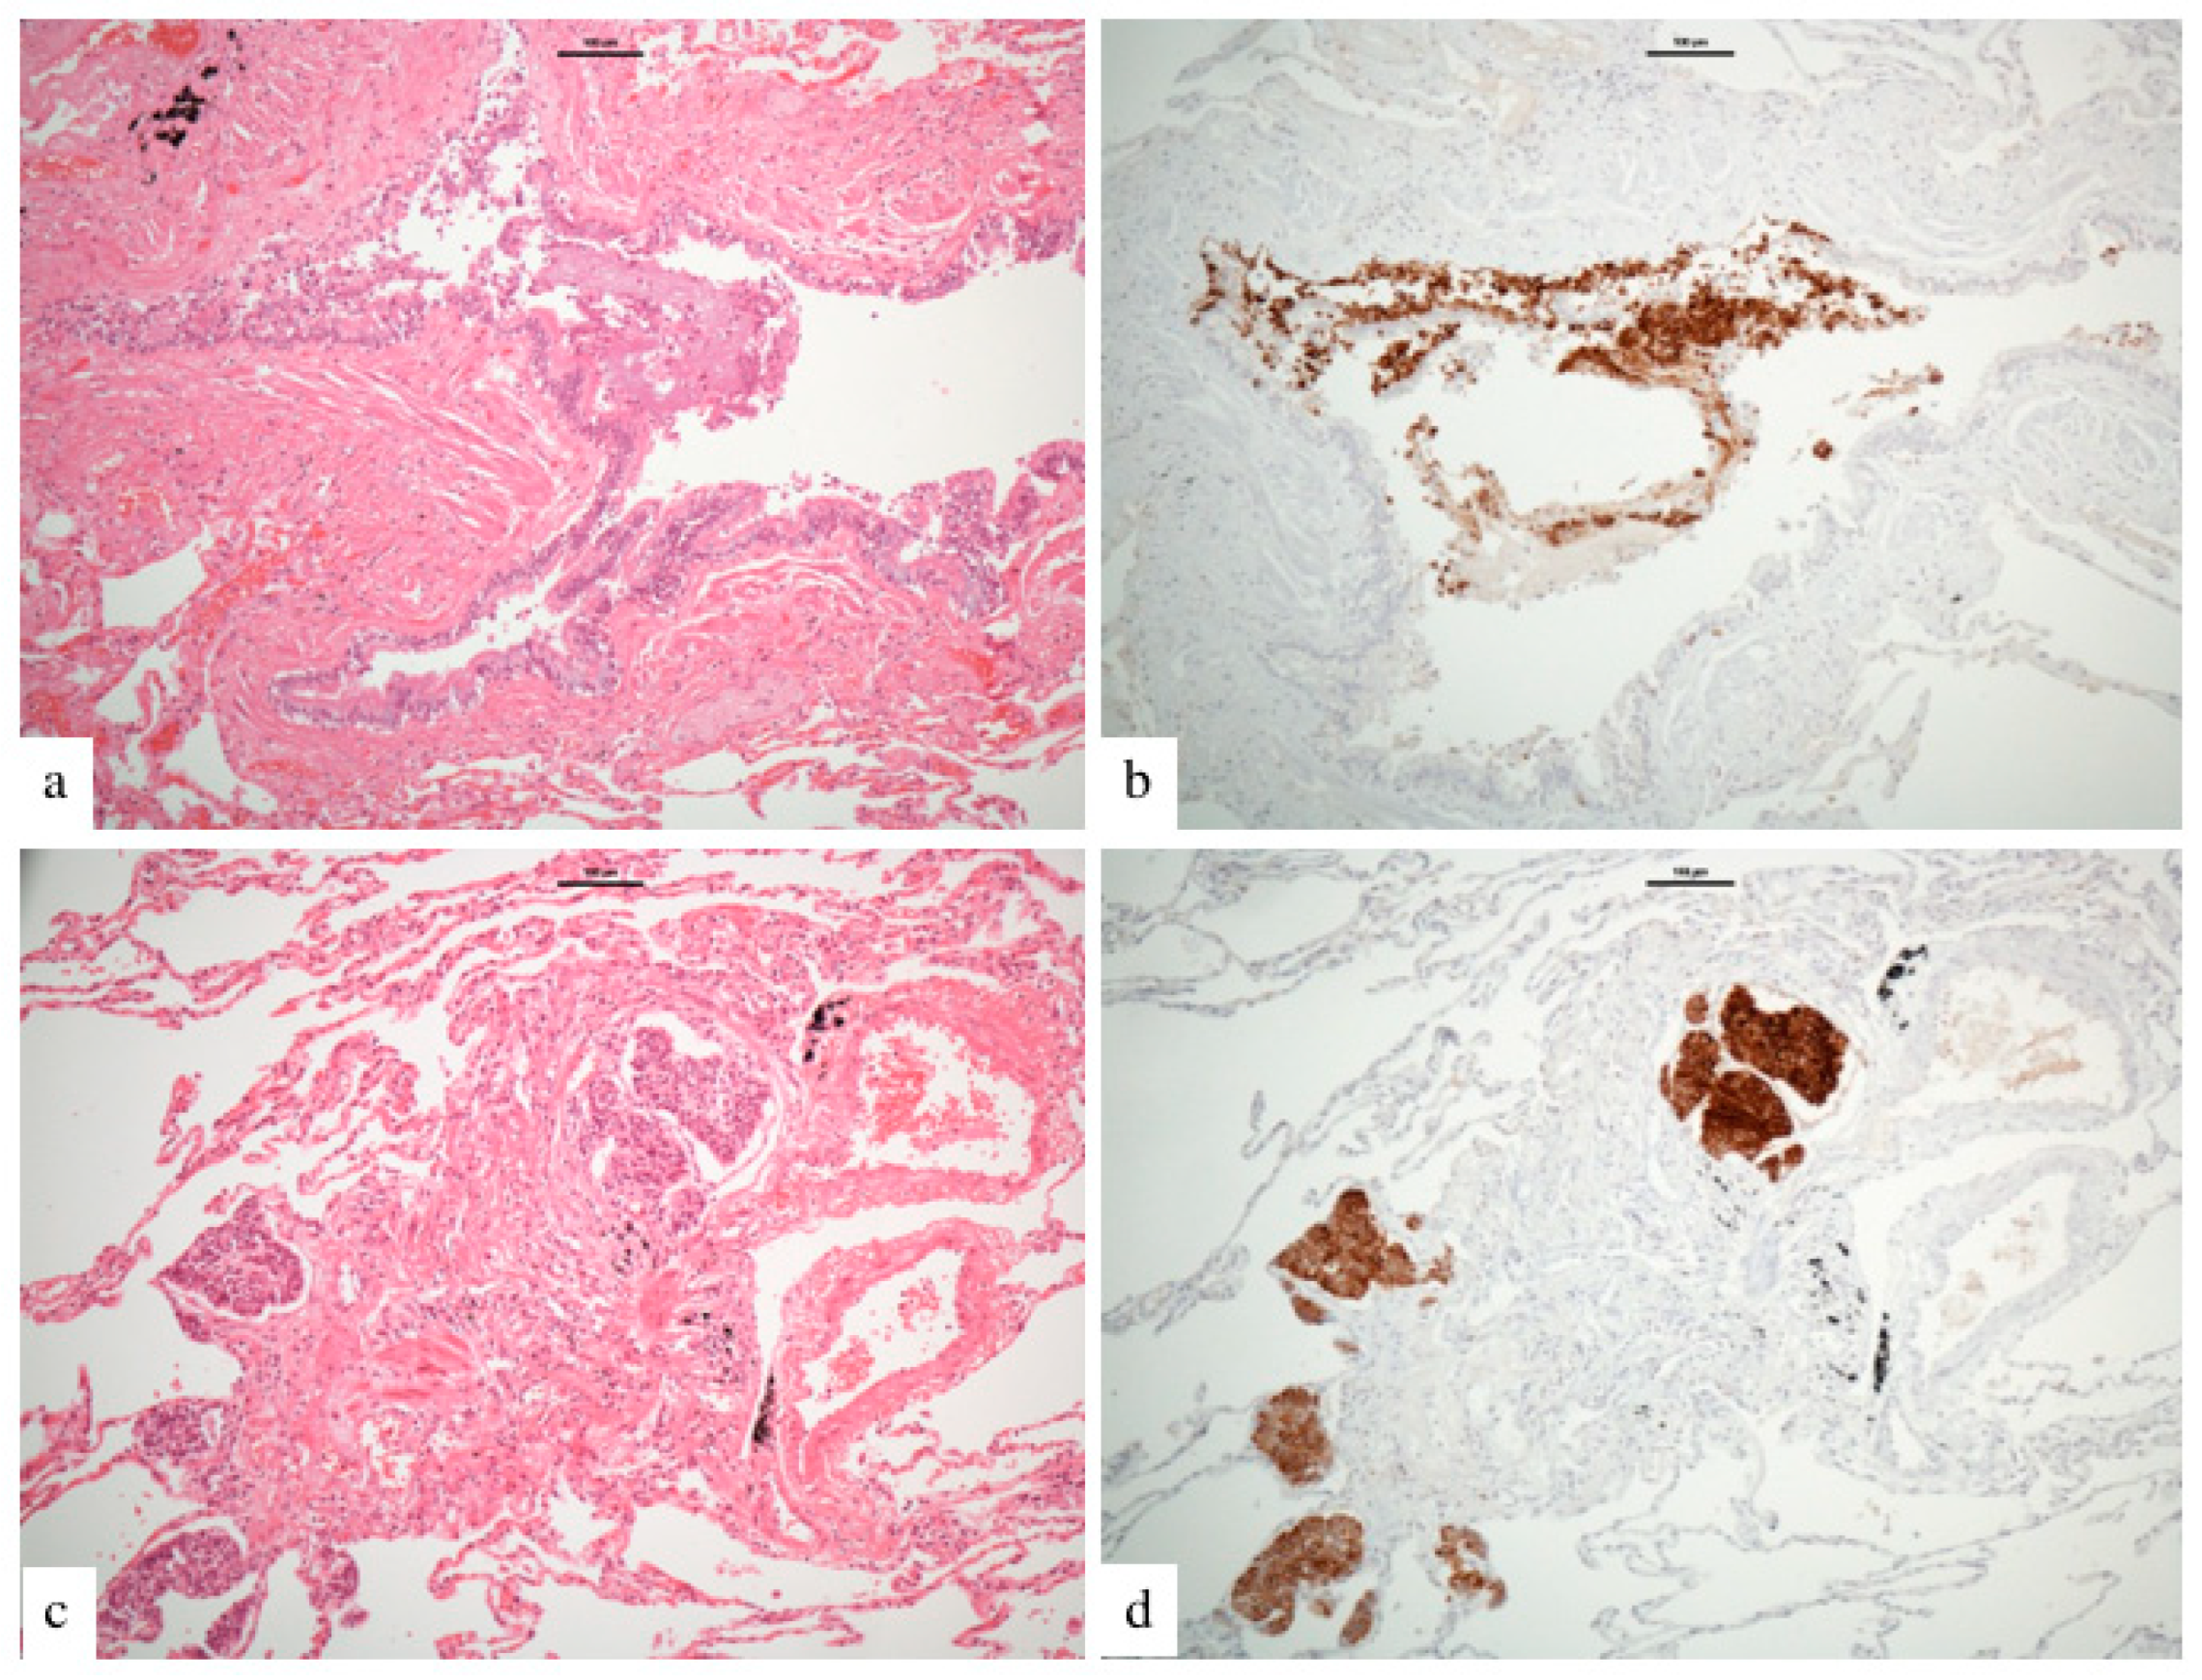

:1. Introduction

3. Results

3.4. Nodule Characteristics